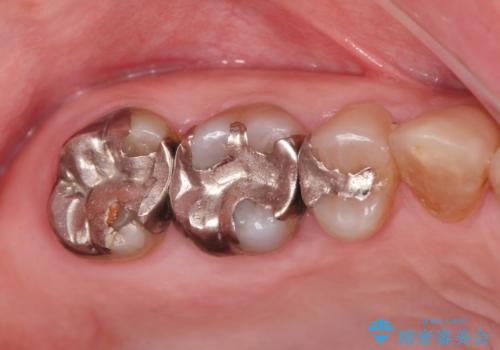

歯周ポケットの除去を歯周外科により行ったのち精度が高く清掃のしやすいセラミック治療による再補綴を行います。

- 42.9万円(ジルコニアクラウン×2・仮歯×2 歯周外科)費用は治療当時の料金となります